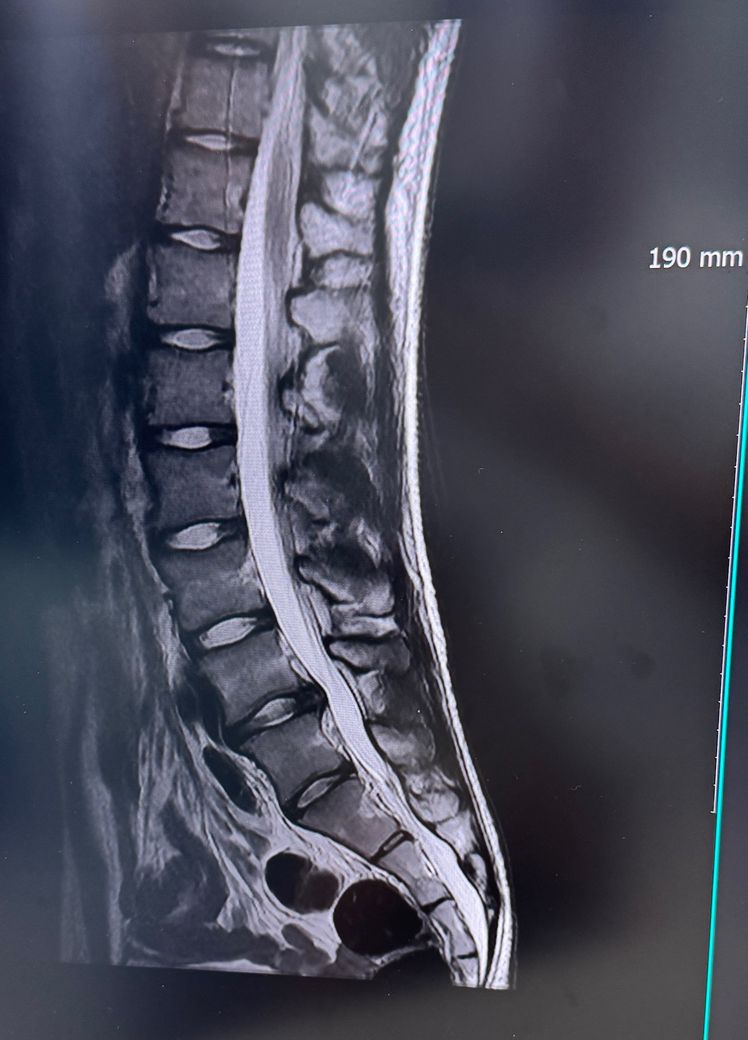

사진으로 봤을때 허리디스크가 심한편인가요? 어느정도 진행된거같나요? 더 심해질수도 있을가요? 지금 허리 통증이 생긴지 8개월 정도 된거같아요 통증이 점점심해지네요 주사치료도 5번 이상 받았습니다

이미 8개월 이상 통증 지속되고 주사 치료도 반복 중이라면 디스크가 꽤 진행된 중등도 이상일 가능성이 높습니다. 자연 회복은 보통 6주에서 3개월 내 호전되지만 그 이상 지속되면 수술 외 치료나 수술적 평가도 필요합니다. 증상이 점점심해진다면 신경 압박이 더 진행될 수 있어 아고하 가능성도 있습니다!

지금으로썬 디스크 돌출 상태로 보여집니다.

다만 가장 정확한것은 MRI 촬영한 병원에 영상전문의에 판독 및 현 담당의에 판독 소견을 들어보시길 바랍니다.

디스크라고 해서 무조건 통증이 있는것은 아니지만 지금 현재 8개월이 지난 상태에서도 통증이 더 심해진다면 허리가 좋은 상태는 아닌것으로 보여집니다.